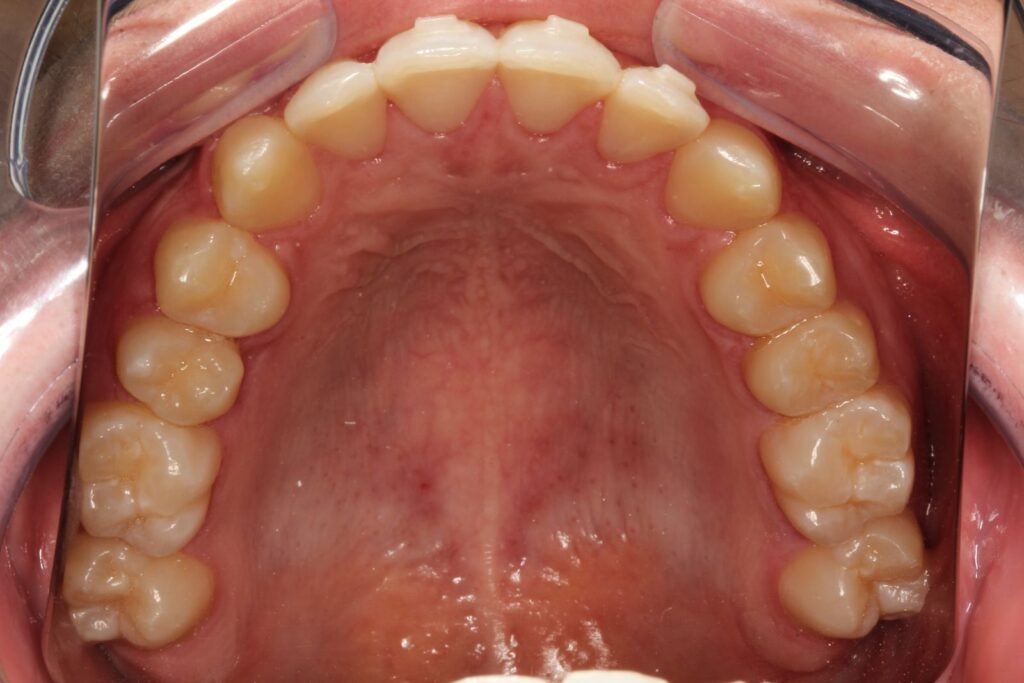

Paciente com tratamento finalizado em 8 meses!

Com disciplina no uso e acompanhamento regular, os resultados costumam aparecer em poucos meses, proporcionando um sorriso alinhado, harmônico e natural.